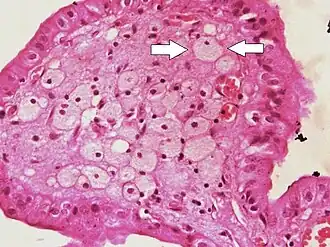

Micrograph of cholesterolosis of the gallbladder, with an annotated foam cell. H&E stain.

The name strawberry gallbladder comes from the typically stippled appearance of the mucosal surface on gross examination, which resembles a strawberry. Cholesterolosis results from abnormal deposits of cholesterol esters in macrophages within the lamina propria (foam cells) and in mucosal epithelium. The gallbladder may be affected in a patchy localized form or in a diffuse form. The diffuse form macroscopically appears as a bright red mucosa with yellow mottling (due to lipid), hence the term strawberry gallbladder. It is not tied to cholelithiasis (gallstones) or cholecystitis (inflammation of the gallbladder).[2]